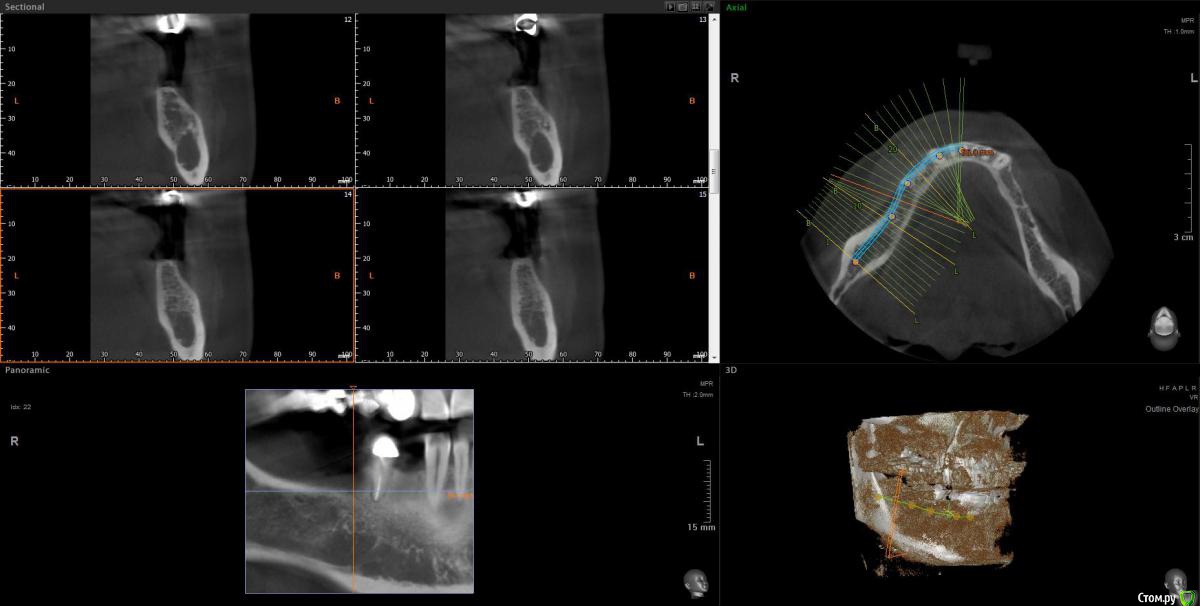

Женька Опубликовано 9 июня, 2020 Поделиться Опубликовано 9 июня, 2020 Тоже спрошу, чтобы не плодить темы.Пришла вот такая пациентка, удаление 28 февраля 2020. Думаю, что ничего страшного и можно ставить не взирая на образование, по крайней мере, мне видится, что это не апексы... тень думаю, потому, что лунка всё еще в стадии заживленияЧто скажете, коллеги? Ссылка на комментарий

Irouil Опубликовано 9 июня, 2020 Поделиться Опубликовано 9 июня, 2020 Как минимум один кусочек чего-то белого на последнем срезе есть Можно ещё прицелку посмотреть. А что с анамнезом? Ссылка на комментарий

Женька Опубликовано 9 июня, 2020 Поделиться Опубликовано 9 июня, 2020 Как минимум один кусочек чего-то белого на последнем срезе есть Можно ещё прицелку посмотреть. А что с анамнезом?В анамнезе у бабушки Cr желудка.Прицела к сожалению нету пломбировочный материал? мне кажется он В остальном считает себя здоровой, по врачам не бегает, на учётах не состоит. Во время удаления (удалял не я) делали прицелы после, и тоже увидели это образование (со слов пациентки). Ссылка на комментарий

Fin Опубликовано 9 июня, 2020 Автор Поделиться Опубликовано 9 июня, 2020 В анамнезе у бабушки Cr желудка.Прицела к сожалению нету пломбировочный материал? мне кажется он В остальном считает себя здоровой, по врачам не бегает, на учётах не состоит. Во время удаления (удалял не я) делали прицелы после, и тоже увидели это образование (со слов пациентки).Удаление 28 было, а когда сделано КТ?. По мне да, лунка в стадии заживления, если вы про дистальное образование то это одонтома, а вот на верхушке гребня что то есть. Думаю что ничего страшного,сделаете прицельный снимок перед имплантацией и если что во время операции уберете. Ссылка на комментарий

red_butler Опубликовано 9 июня, 2020 Поделиться Опубликовано 9 июня, 2020 Что скажете, коллеги? я бы удалил и возможно на гистологию отправил 2 Ссылка на комментарий

Женька Опубликовано 9 июня, 2020 Поделиться Опубликовано 9 июня, 2020 Удаление 28 было, а когда сделано КТ?. По мне да, лунка в стадии заживления, если вы про дистальное образование то это одонтома, а вот на верхушке гребня что то есть. Думаю что ничего страшного,сделаете прицельный снимок перед имплантацией и если что во время операции уберете.Кт от 8 июня. я бы удалил и возможно на гистологию отправилИз-за анамнеза родословной? Ссылка на комментарий

red_butler Опубликовано 9 июня, 2020 Поделиться Опубликовано 9 июня, 2020 Кт от 8 июня. Из-за анамнеза родословной?Нет, новообразование имеет оболочку, не хотелось бы удалять имея там имплант 1 Ссылка на комментарий

Женька Опубликовано 9 июня, 2020 Поделиться Опубликовано 9 июня, 2020 Записал срезы Кт, вижу что-то похожее на корень с ярким материалом в области края гребня. И образование, по плотности как кортика. + лунки заживающие. Ссылка на комментарий

red_butler Опубликовано 9 июня, 2020 Поделиться Опубликовано 9 июня, 2020 https://youtu.be/1pW5wBBAbls Записал срезы Кт, вижу что-то похожее на корень с ярким материалом в области края гребня. И образование, по плотности как кортика. + лунки заживающие.Похоже на корень. А есть снимки до удаления? И настораживает, зачем коллеги делали rg после удаления.., Ссылка на комментарий

Женька Опубликовано 9 июня, 2020 Поделиться Опубликовано 9 июня, 2020 Похоже на корень. На верхушке гребня с ярким рентгеноконтрастным материалом? или где-то в другом месте? А есть снимки до удаления? Была вроде ОПТГ, попробую вытянуть у пациентки.И настораживает, зачем коллеги делали rg после удаления..,Именно из-за этого плотного образования. Ссылка на комментарий

Женька Опубликовано 10 июня, 2020 Поделиться Опубликовано 10 июня, 2020 А есть снимки до удаления? Можно ещё прицелку посмотреть. Прицелки нет, как я сказал, но есть ОПТГ до удаления, правда не лучшего качества... Ссылка на комментарий

Irouil Опубликовано 10 июня, 2020 Поделиться Опубликовано 10 июня, 2020 я бы удалил и возможно на гистологию отправилТут мне кажется верное решение Похоже на какую-то цементому не удалённую, но все же Ссылка на комментарий

Женька Опубликовано 10 июня, 2020 Поделиться Опубликовано 10 июня, 2020 Тут мне кажется верное решение Похоже на какую-то цементому не удалённую, но все жеВозможно меня неправильно поняли) у бабушки пациентки был Cr в анамнезе...Или разницы нет и не стоит имплантировать пока не уберу образование?Но тогда другой вопрос, как оптимальнее его вытащить? или не важно и всё равно придется аугментировать и ждать? Ссылка на комментарий

Irouil Опубликовано 10 июня, 2020 Поделиться Опубликовано 10 июня, 2020 Возможно меня неправильно поняли) у бабушки пациентки был Cr в анамнезе...Или разницы нет и не стоит имплантировать пока не уберу образование?Но тогда другой вопрос, как оптимальнее его вытащить? или не важно и всё равно придется аугментировать и ждать?Про бабушку я понял. Но если эта штука осумкована (а на орто до тоже так кажется), то вокруг импланта пойдёт расти ее капсула, а не кость. По крайней мере есть такой риск. Ну а на гистологию всегда лучше сдать, чем не сдать Ссылка на комментарий

Женька Опубликовано 10 июня, 2020 Поделиться Опубликовано 10 июня, 2020 Про бабушку я понял. Но если эта штука осумкована (а на орто до тоже так кажется), то вокруг импланта пойдёт расти ее капсула, а не кость. По крайней мере есть такой риск. Ну а на гистологию всегда лучше сдать, чем не сдатьРазницы крестально идти или вестибулярно особенной нет? Всё равно через аугментацию и отсроченно имплантировать? Ссылка на комментарий

Irouil Опубликовано 10 июня, 2020 Поделиться Опубликовано 10 июня, 2020 Сложно сказать. Наверное - крестально, там мягко, судя по снимку, да и дефект с лучшим прогнозом. Главное чтобы не слишком глубоко и узко для доступа было Ссылка на комментарий

Женька Опубликовано 10 июня, 2020 Поделиться Опубликовано 10 июня, 2020 Главное чтобы не слишком глубоко и узко для доступа былоИ если так, то придется расширять и копаться или добавлять вестибулярный доступ Ссылка на комментарий